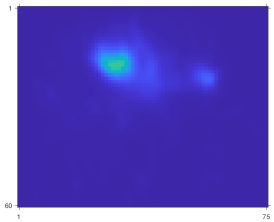

Fig. 9 compares the reconstruction quality between OSEM and CNN-regularized EM algorithm using sequential training, gradient truncation and end-to-end training. Visually, the end-to-end training reconstruction yields the closest estimate to the true activity. This is also evident through the line profiles (subfigure (m) and (n)) across the tumor and the liver.

Refer to caption

Figure 9: Qualitative comparison of different training methods and OSEM tested on Y90superscriptY90{}^{90}\mathrm{Y} VP phantoms. Subfigure (a)-(f) and (g)-(l) show two slices from two testing phantoms. Subfigure (m) and (n) correspond to line profiles in (a) and (g), respectively.

Table III reports the mean activity error (MAE) and NRMSE for lesions and organs across all testing phantoms. Similar to the qualitative assessment (Fig. 9), the end-to-end training also produced lower errors consistently across all testing lesions and organs. For instance, compared to sequential training/gradient truncation, the end-to-end training relatively reduced MAE on average by 8.7%/7.2%, 18.5%/11.0% and 24.7%/16.1% for lesion, healthy liver and lung, respectively. The NRMSE was also relatively reduced by 6.1%/3.8%, 7.2%/4.1% and 6.1%/3.0% for lesion, healthy liver and lung, respectively. All learning-based methods consistently had lower errors than the OSEM method.